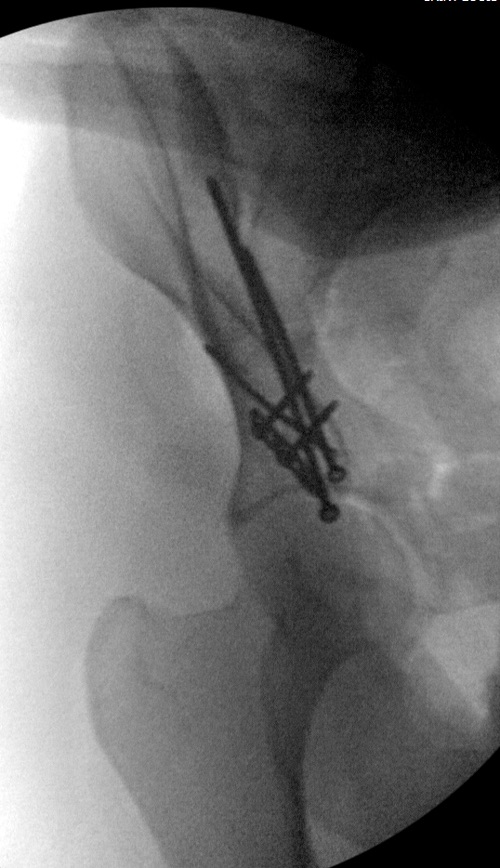

Это высокий перелом передней колонны вертлужной впадины (62A3.2).

Появились новые проекции. Да, это высокий перелом передней колонны левой вертлужной впадины со смещением.

Да, я понимаю, что предпочтительнее всего накостный синтез. Но если сравнивать АВФ с миниинвазивным, то ни тот ни другой не гарантируют 100%й репозиции. Перелом начинается с передней стенки впадины, идет вверх до крыла, а сзади спускаясь, останавливается едва достигнув задней колонны. Да, задняя колонна цела. Есть поперечные срезы КТ (сейчас показать не могу), где это четко видно. Перелом не завершенный. Учитывая этот факт, я и подумал о возможности АВФ. Простите мне мою упрямость)).

Относительно диагноза соглашусь с коллегами повреждение крыла и передней колоны вертлужной впадины ближе к типу В по классификации Летурнеля, хотя не в полной мере ей соответствует. Согласно Матта смещение более 3х мм -показание к открытому остеосинтезу, в данном случае скорее из илиоингвинального доступа или Стоппа. Хотелось бы конечно увидеть остальные срезы и рентгенограммы.

Данная картина показывает очень редкий перелом передней колонны, но перед операцией еще раз надо просмотреть обещанные дополнительные КТ срезы.